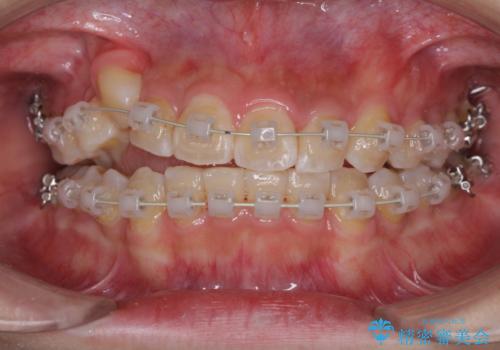

- 矯正装置

- 審美装置

- 治療期間

- 2年10ヶ月